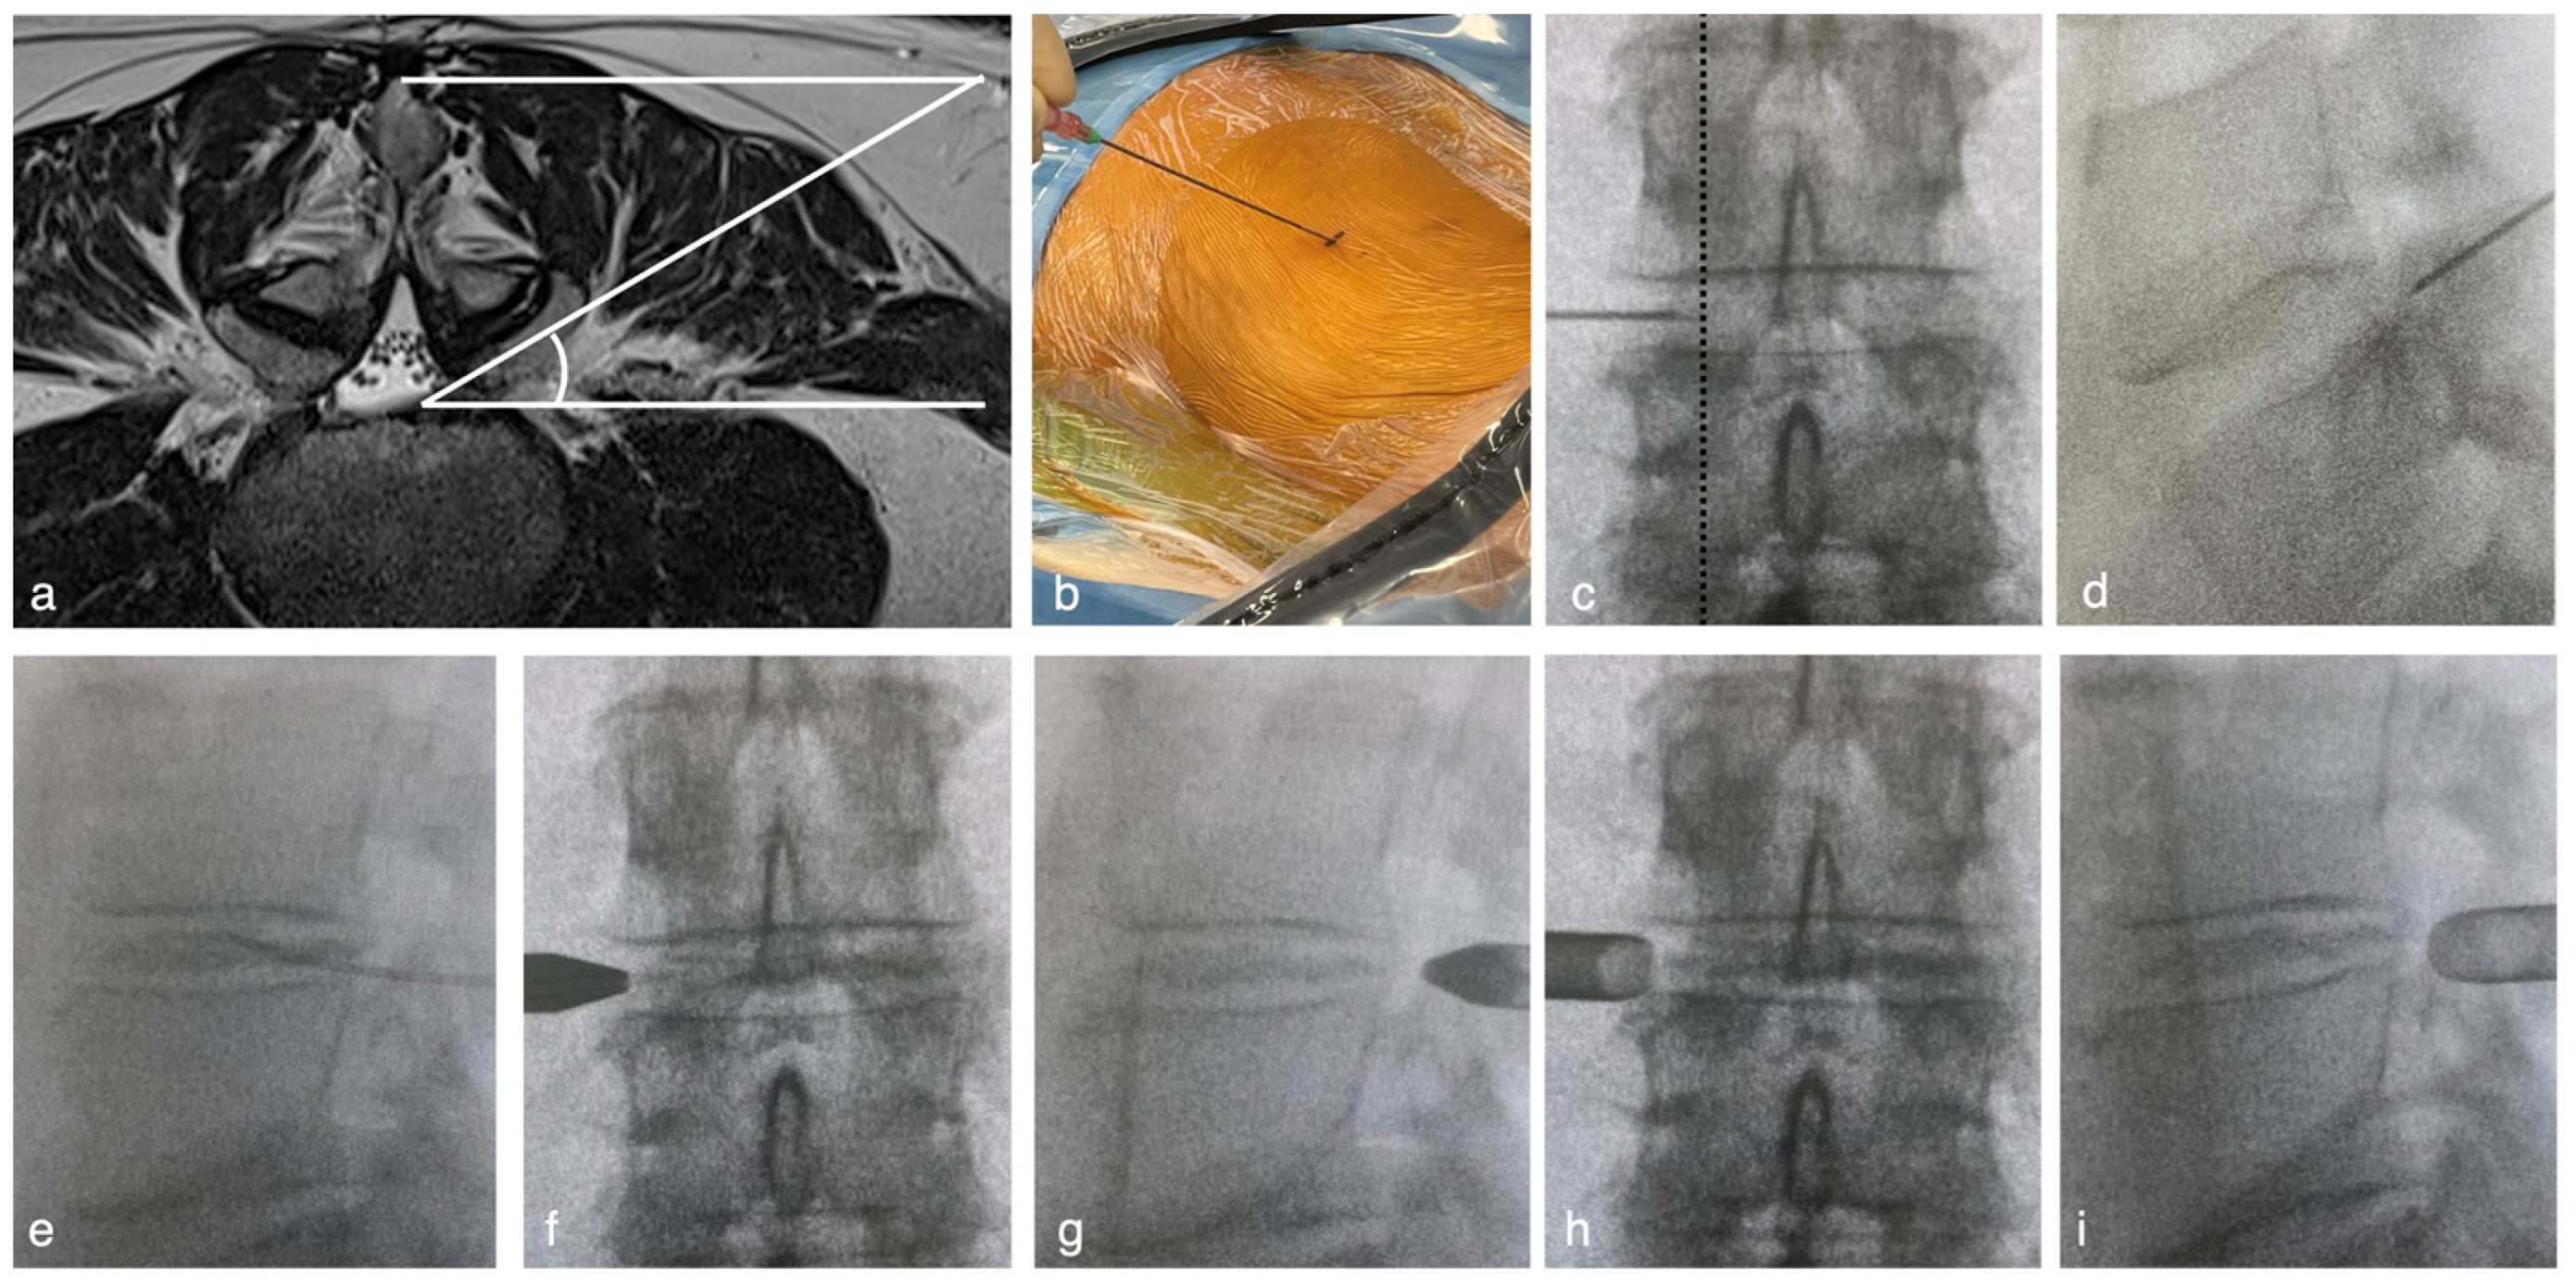

- The entry point was determined to be 8–13 cm from the midline to acquire 45° from the horizontal line (Figure 1a). The spinal needles were inserted from the entry point until they reached the lateral aspect of the superior articular process (SAP) (Figure 1b). The needle tip was inserted into the foramen and slid along the ventral part of the facet joint (Figure 1c,d). Needle entry into the intervertebral disc should be more internal than the medial line of the cranial and caudal pedicles in the A-P and lateral views. The needle was advanced. The nucleus pulposus was stained with saline, indigo carmine, and an imaging agent (Figure 1e). Preoperative discography clarifies the difference between herniated fragments and other soft tissues under an endoscopic view.

- The needle was replaced with a guidewire, and an approximately 3 cm incision was made at the entry point. A pencil dilator was then inserted along the guidewire (Figure 1f,g). The guidewire was removed after the tip of the pencil dilator touched the superior facet. A bevel-type cannula was inserted using a pencil dilator (Figure 1h,i). Finally, the endoscope was introduced.